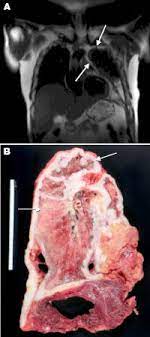

In the largest study to date on the link between firefighting foam and kidney cancer risk, researchers found evidence to suggest that people with higher concentrations of pfas in their blood serum were more than twice as likely to develop kidney cancer compared to those with lower concentrations of the chemicals. Here, we report the case of a kidney transplant patient for 2 years with malignant pleural effusion that was subsequently diagnosed as malignant pleural mesothelioma. Malignant mesothelioma is a rare cancer with no cure. The less common, peritoneal mesothelioma, is found in the lining of the abdomen, and is generally harder to treat. Neuroendocrine tumor of the lung; Relative risk for each cancer by Research applications in the areas of breast, prostate, lung (excluding mesothelioma), kidney, melanoma, pancreatic, rare cancer, or ovarian cancer will not be accepted. It is not a lung cancer but it is a cancer of the covering of the lung that is known as a pleura. Melanoma, sarcoma, kidney cancer, merkel cell carcinoma. mesothelioma meme,mesothelioma causes,mesothelioma definition,mesothelioma symptoms,mesothelioma prognosis,mesothelioma treatment,mesothelioma what is it,mesothelioma lawsuit,mesothelioma survival rates,mesothelioma law firm,mesothelioma,mesothelioma commercial,mesothelioma cancer,mesothelioma ad,mesothelioma ad script,mesothelioma awareness,mesothelioma applied research foundation. What kind of cancer is a pleural mesothelioma? See more ideas about mesothelioma, treatment, cancer. Navy ships built before 1980.

It is intended as a resource to inform and assist clinicians who care for cancer patients. Research applications in the areas of breast, prostate, lung (excluding mesothelioma), kidney, melanoma, pancreatic, rare cancer, or ovarian cancer will not be accepted. Malignant pleural mesothelioma is a malignant or cancerous tumor of the pleura, the mesothelium that surrounds the lungs. Allogeneic tumor cell vaccine biological: Peritoneal mesothelioma begins with tumor development in the peritoneum, the thin.

Renal cancer is a cancer of the cell lining (epithelial cells) of the kidney. Pericardial mesothelioma is a rather rare type of mesothelioma and accounts for around 5% of all instances of mesothelioma. Pleural mesothelioma occurs in the lining of the lung and accounts for approximately 75 percent of all cases. mesothelioma meme,mesothelioma causes,mesothelioma definition,mesothelioma symptoms,mesothelioma prognosis,mesothelioma treatment,mesothelioma what is it,mesothelioma lawsuit,mesothelioma survival rates,mesothelioma law firm,mesothelioma,mesothelioma commercial,mesothelioma cancer,mesothelioma ad,mesothelioma ad script,mesothelioma awareness,mesothelioma applied research foundation. When we mimic the effects of bap1 mutation in xenopus laevis (african clawed frog) embryos, they develop a striking appearance that is easy to. Melanoma, sarcoma, kidney cancer, merkel cell carcinoma. In rare cases, mesothelioma can occur in the pericardium, the lining of the heart. Research applications in the areas of breast, prostate, lung (excluding mesothelioma), kidney, melanoma, pancreatic, rare cancer, or ovarian cancer will not be accepted. In 8 cases, adenocarcinoma with unknown origin and in 7 cases malignant pleural mesothelioma had caused the pleural effusion. Lung cancer is the uncontrolled growth of abnormal cells (a malignant tumor) that begins in the cells of the lungs. Nicholas vogelzang, md, fasco, facp has dedicated his professional life to researching and treating rare forms of cancer. Navy ships built before 1980. The inclusion of the individual rare cancer research program shall not prohibit the prcrp from funding the below mentioned cancers or cancer subtypes that may be rare by.